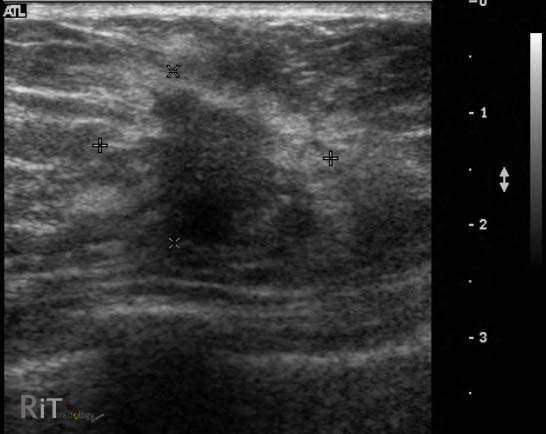

El ultrasonido mamario se centra específicamente en la evaluación de las mamas y los tejidos circundantes. Este procedimiento se utiliza principalmente para detectar y caracterizar anormalidades mamarias, como bultos, quistes o masas, y para guiar procedimientos invasivos, como biopsias mamarias.

En cuanto a la técnica de imagen, tanto el ultrasonido mamario como la ecografía de mama utilizan ultrasonido de alta frecuencia para generar imágenes en tiempo real de los tejidos mamarios. Sin embargo, el ultrasonido mamario puede emplear técnicas y configuraciones específicas diseñadas para optimizar la visualización de las mamas y sus estructuras.

En muchos casos, el ultrasonido mamario y la ecografía de mama se utilizan de manera complementaria para proporcionar una evaluación completa de las mamas y sus estructuras asociadas. Por ejemplo, el ultrasonido mamario puede detectar y caracterizar una anomalía mamaria, mientras que la ecografía de mama puede evaluar los ganglios linfáticos axilares para detectar signos de metástasis en el cáncer de mama.